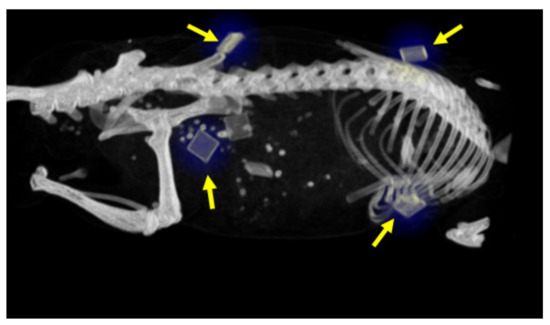

| Mouse ID | Modality | Current (mA) |

| 1 | Standard | 0.2 |

| 2 | Good | 0.2 |

| 3 | Best | 0.2 |

| 4 | Standard | 0.4 |

| 5 | HR | 0.4 |